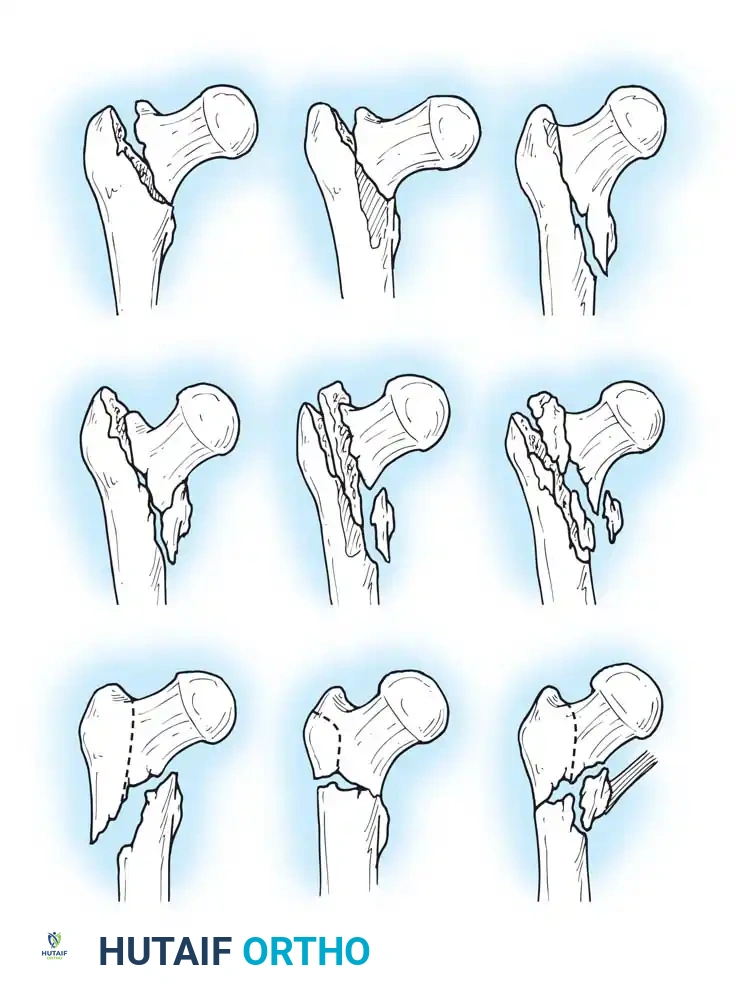

Fig. 52-4: AO Classification of trochanteric fractures. A1 (simple), A2 (comminuted), and A3 (reverse obliquity/transverse).

- 31-A1: Simple, two-part fractures (Stable).

- 31-A2: Comminuted fractures with posteromedial fragmentation (Unstable).

- 31-A3: Reverse obliquity or transverse fractures extending into the lateral cortex (Highly Unstable).